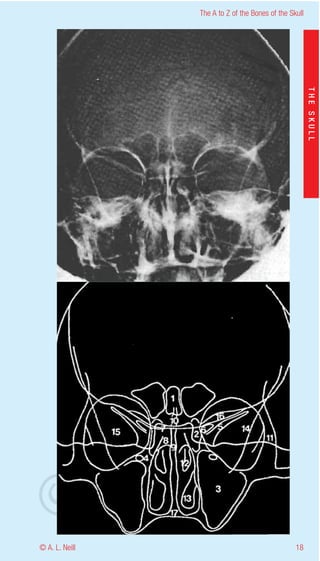

The A to Z of the Bones of the Skull

eill

THE SKULL

aN

nd

ma

rA

©D

© A. L. Neill                                        18

External Skull Anterior

upper and lower views in detail

radiology occipitomental (lower)

1           Frontal sinus

2           Ethmoid sinus

3           Maxillary sinus

4           Foramen rotundum

5           Supraorbital fissure

6           Anterior clinoid process

7           Posterior clinoid process

8           Petrous ridge

9           Floor of the hypophyseal fossa + upper apex of

nasal cavity adjacent to nasal sinuses

10          Crista galli

11          Frontal process of zygoma

12          Middle concha - turbinate

13          Inferior concha - turbinate

14          Lateral border of Greater wing of sphenoid

15          Greater wing of sphenoid

16          Lesser wing of sphenoid

17          Hard palate

18          Infraorbital foramen

19          Zygomaticofacial foramen

20          Coronoid process of the mandible

21          Soft tissue of lower lid

22          Pterygoid plates of the sphenoid

19                                                        © A. L. Neill